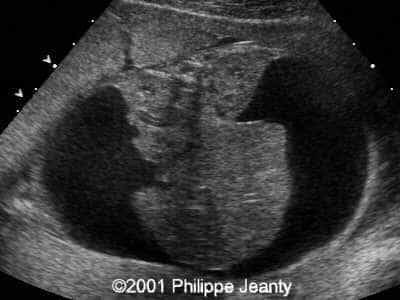

This 2nd trimester fetus has the following images (actually, these images remained unchanged for several weeks)

• very enlarged lungs on both sides

• inversion of the diaphragm that is convex towards the abdomen

• small compressed heart

• ascites but no generalized hydrops (no skin thickening for instance)

A common diagnosis for brightly echogenic lungs is Congenital lobar adenomatosis, type III. Yet this diagnosis is usually unilateral and not bilateral (although Congenital lobar adenomatosis, bilateral, type III can happen).

A much more common diagnosis for a bilateral echogenic lung associated with microcardia and ascites (Budd-Chiari phenomenon) is Larynx, atresia or as reported by several the CHAOS syndrome which stands for Congenital High Airway Obstruction Syndrome (which is typically laryngeal or tracheal atresia). This is the diagnosis that was indeed suspected in this fetus.